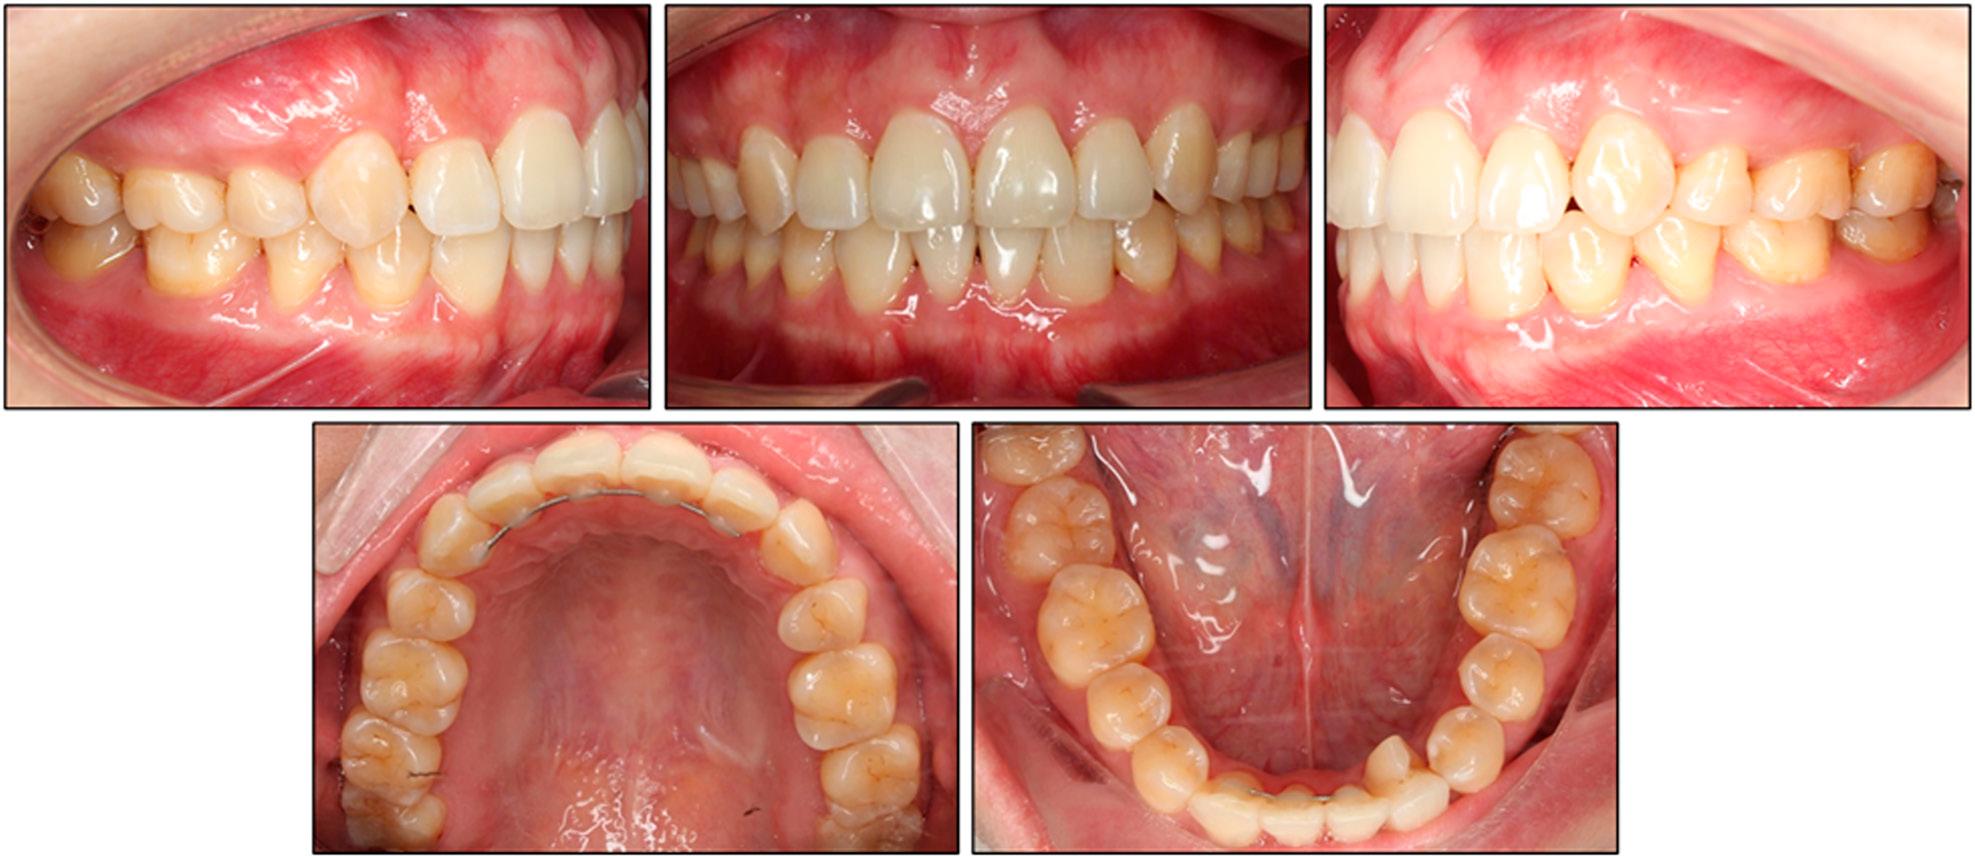

Post-treatment extra- and intra-oral clinical photographs.

Intra-orally, a stable bilateral Angle Class I molar and functional “canine” relationship was achieved (Figure 6). The mandibular dental midline was successfully moved to the left to co-incide with the maxillary and facial midlines. Overjet finished at 2.6 mm and overbite at 2.3 mm, both of which were within normal limits, and the severe maxillary crowding was resolved. The rotated left fused tooth aligned harmoniously with its neighbours, and the arch forms were well co-ordinated.